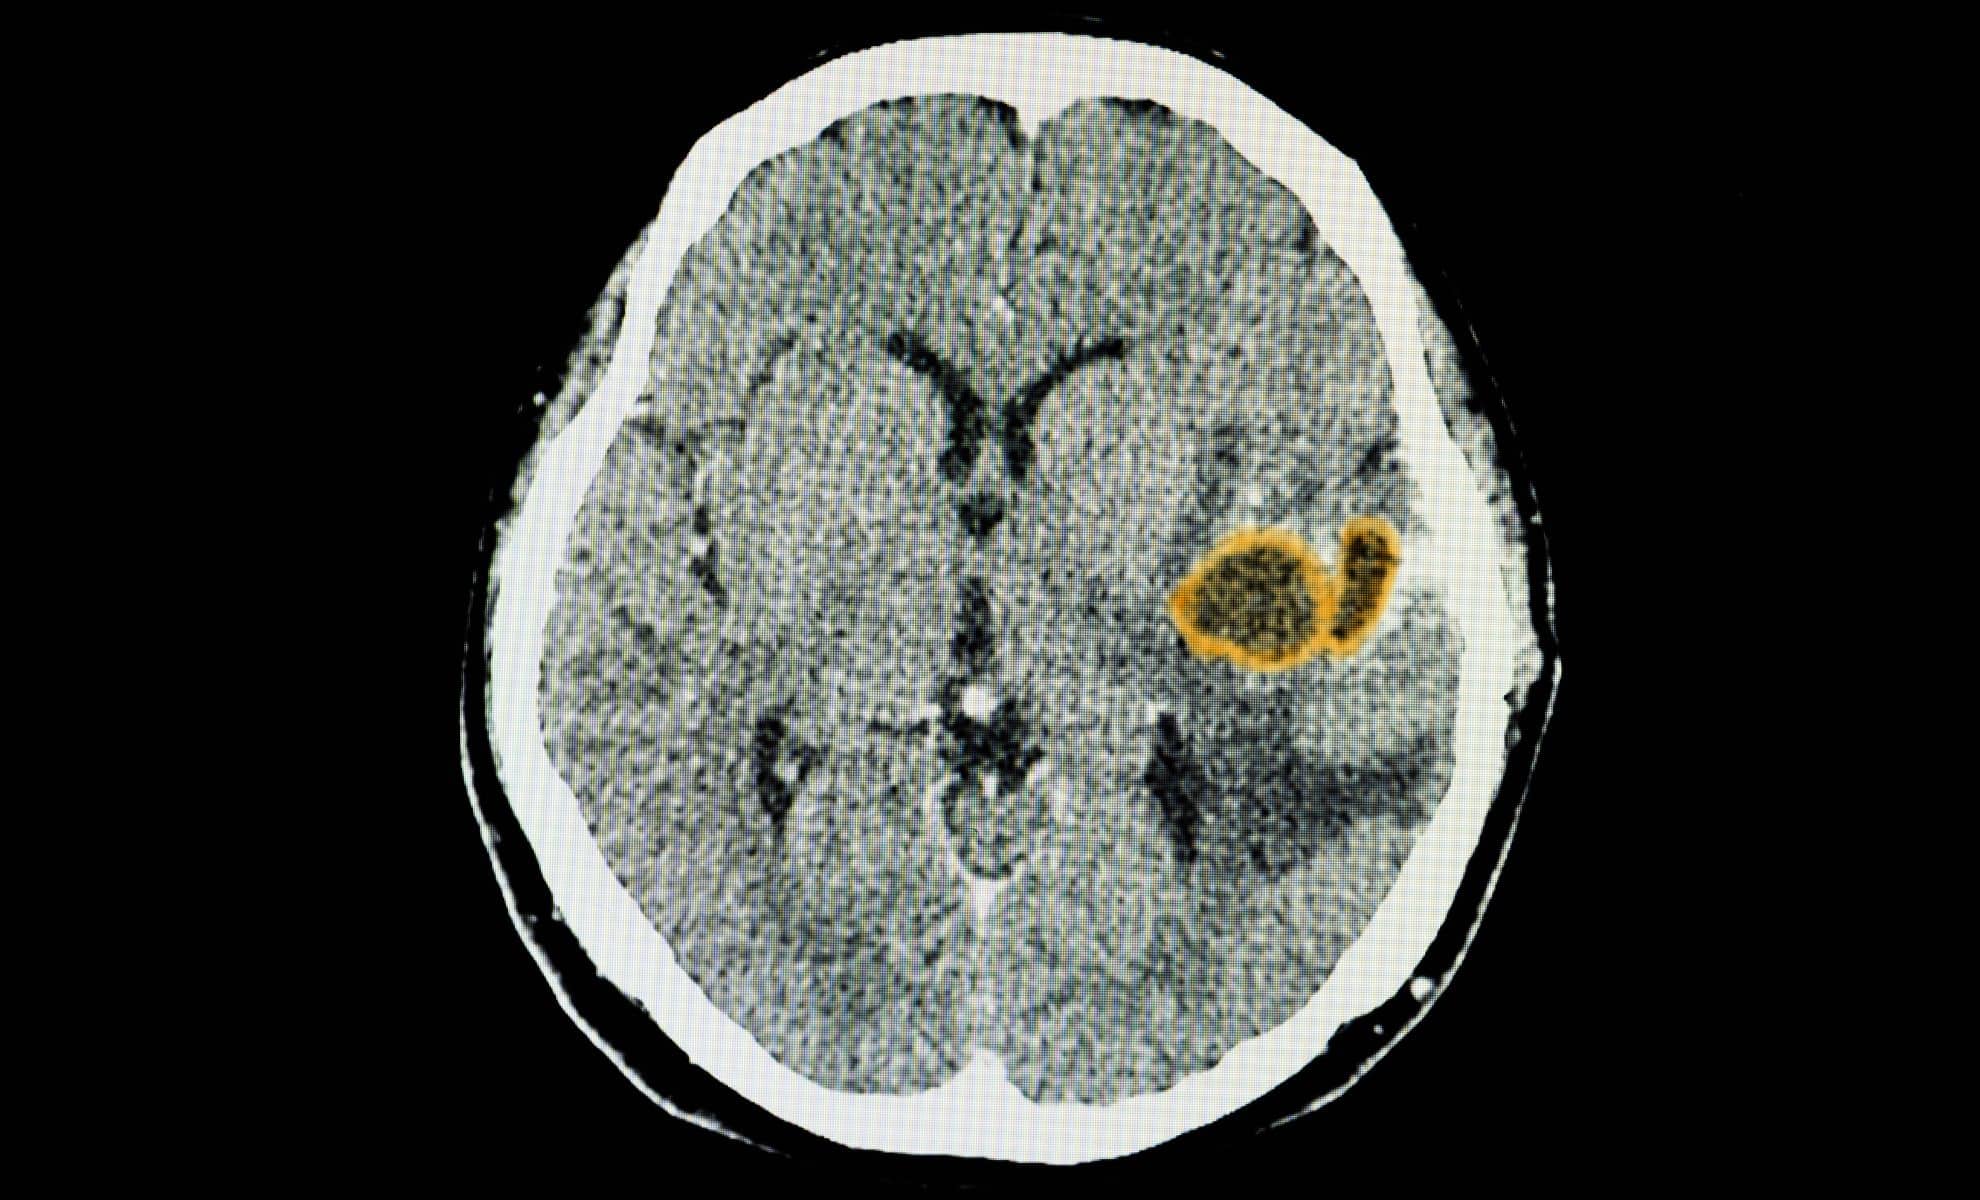

This research sheds light on how the body protects itself from Toxoplasma gondii, a parasite estimated to infect nearly a third of the global population. While it rarely causes symptoms in healthy individuals, it can become deadly for those with compromised immune systems. The new findings explain why some immune responses fail and how the body keeps this chronic invader under control.

T. gondii typically enters the body through contaminated food or cat exposure, spreading through tissues before establishing a lasting presence in the brain. The University of Virginia research team, led by Dr. Tajie Harris, discovered that the parasite is capable of infecting CD8+ T cells, which are usually tasked with destroying infected cells. Understanding how these cells resist infection, or fail to, has implications for treating at-risk patients.

In mice lacking caspase-8, the parasite’s presence in the brain soared. Despite generating a strong immune response, those mice became seriously ill and died, their brains filled with infected T cells. By contrast, mice with functioning caspase-8 survived, their immune cells clearing the infection effectively.

The enzyme caspase-8 is best known for initiating apoptosis, a self-destruct program within cells. But its role in immune defense, especially in the brain, has only recently come into focus. According to UVA researchers, mice engineered to lack this enzyme showed an eightfold increase in brain parasite load compared to their normal counterparts.